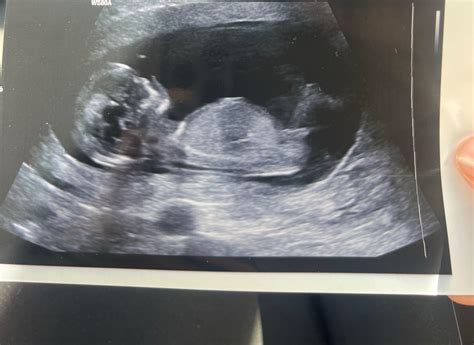

- Ultrazvukový screening druhého trimestra (morfologický ultrazvuk): Medzi 20. až 22. týždňom.

- 3D alebo 4D ultrazvuk: Ideálne medzi 24. až 30. týždňom.

Kedy sa robí 3D alebo 4D ultrazvuk?

Ideálna doba na vykonanie 3D alebo 4D ultrazvuku je medzi 24. až 30. týždňom tehotenstva, kedy je bábätko najlepšie viditeľné.